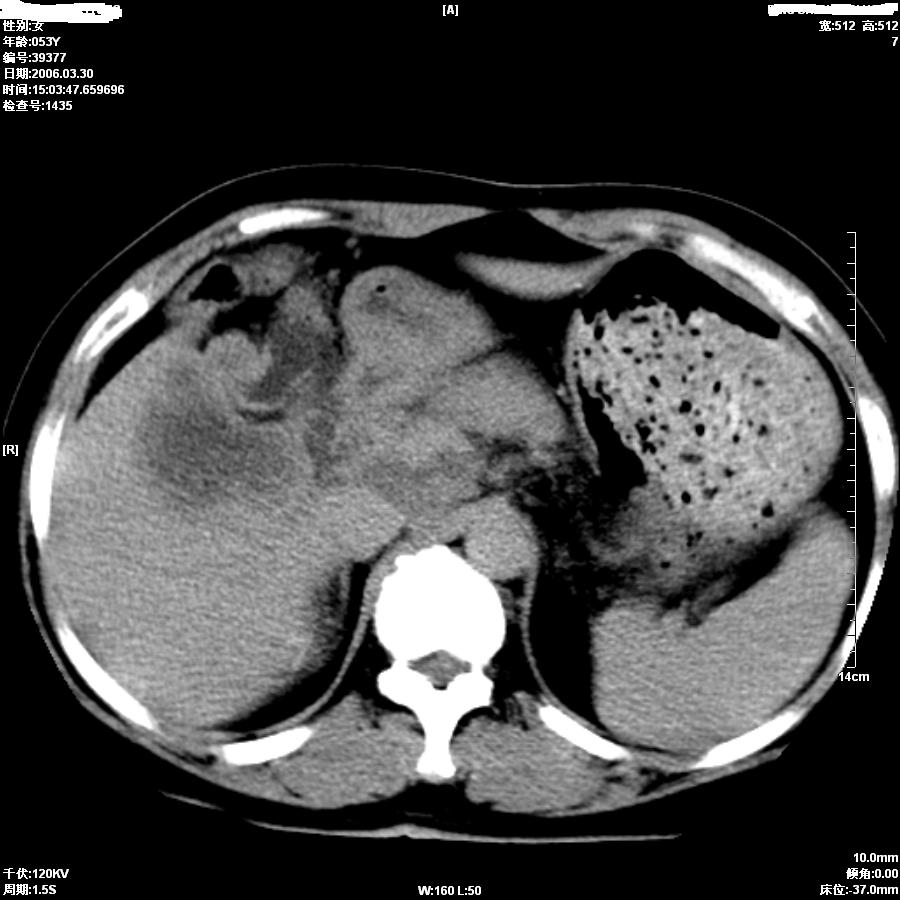

女,50岁,上腹部憋胀,疼痛月余。做增强刚打了50ml造影剂病人就出现了较重的过敏,所以强化不成功。

支持肝癌伴左叶外侧段肝内胆管轻度扩张。

平扫第8图胆总管内似见结石,上部胆道扩张,肝内片影无强化,胆囊不清,胃小弯壁略厚。

考虑1胆结石伴低微弹道梗阻及肝内感染2胆管癌。

因为没有完整的强化,该病例我首先考虑是肝内胆管细胞癌.患者因为有过敏我建议行mri.

从平扫:肝脏肿块,胰头周围结构不清似有结节。考虑恶性肿瘤(首先要排外肝胆感染病变)。胆管癌>肝癌。建议mri。

较典型胆管癌。

胆管细胞癌可能性大

胆总管扩张,未见明显结石征象。还是胆管细胞ca可能大

提示肝内胆管细胞癌。

肝内胆管癌 累及肝门

如果胆囊未切除,首先考虑胆囊癌肝侵犯。

中老年妇女,肝门、胆囊区病变,病变实体形态欠清楚,胆囊癌可能性极大。

鉴别诊断:肝癌;胆管癌;

理由:1、低密度病灶,动脉期末有一点强化。

2、左肝内胆管扩张。

3、肝门区胆管壁静脉期有强化。